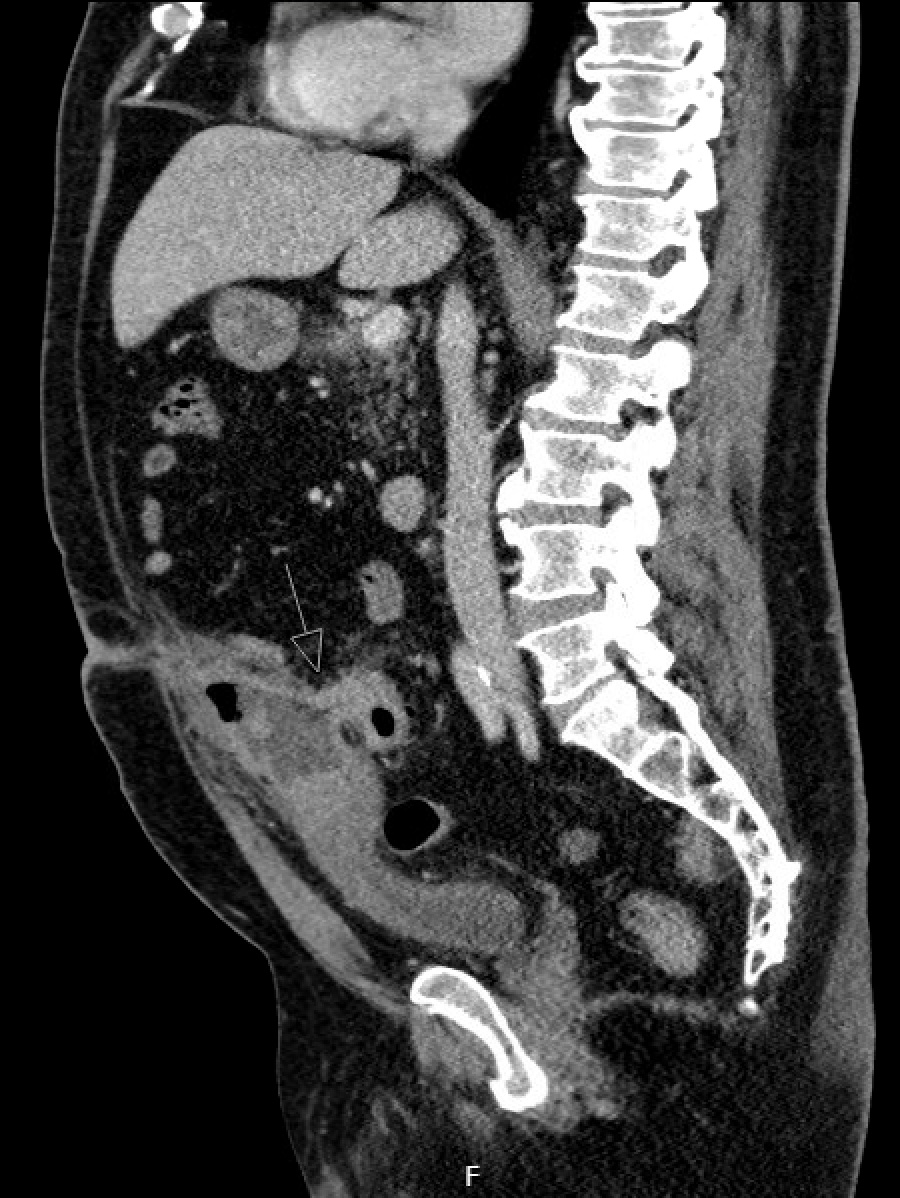

Sagittal CT image demonstrating urachal cyst and abscess with fistula to the sigmoid colon

The image demonstrates the quality of the drainage that was coming from the patient's umbilicus.